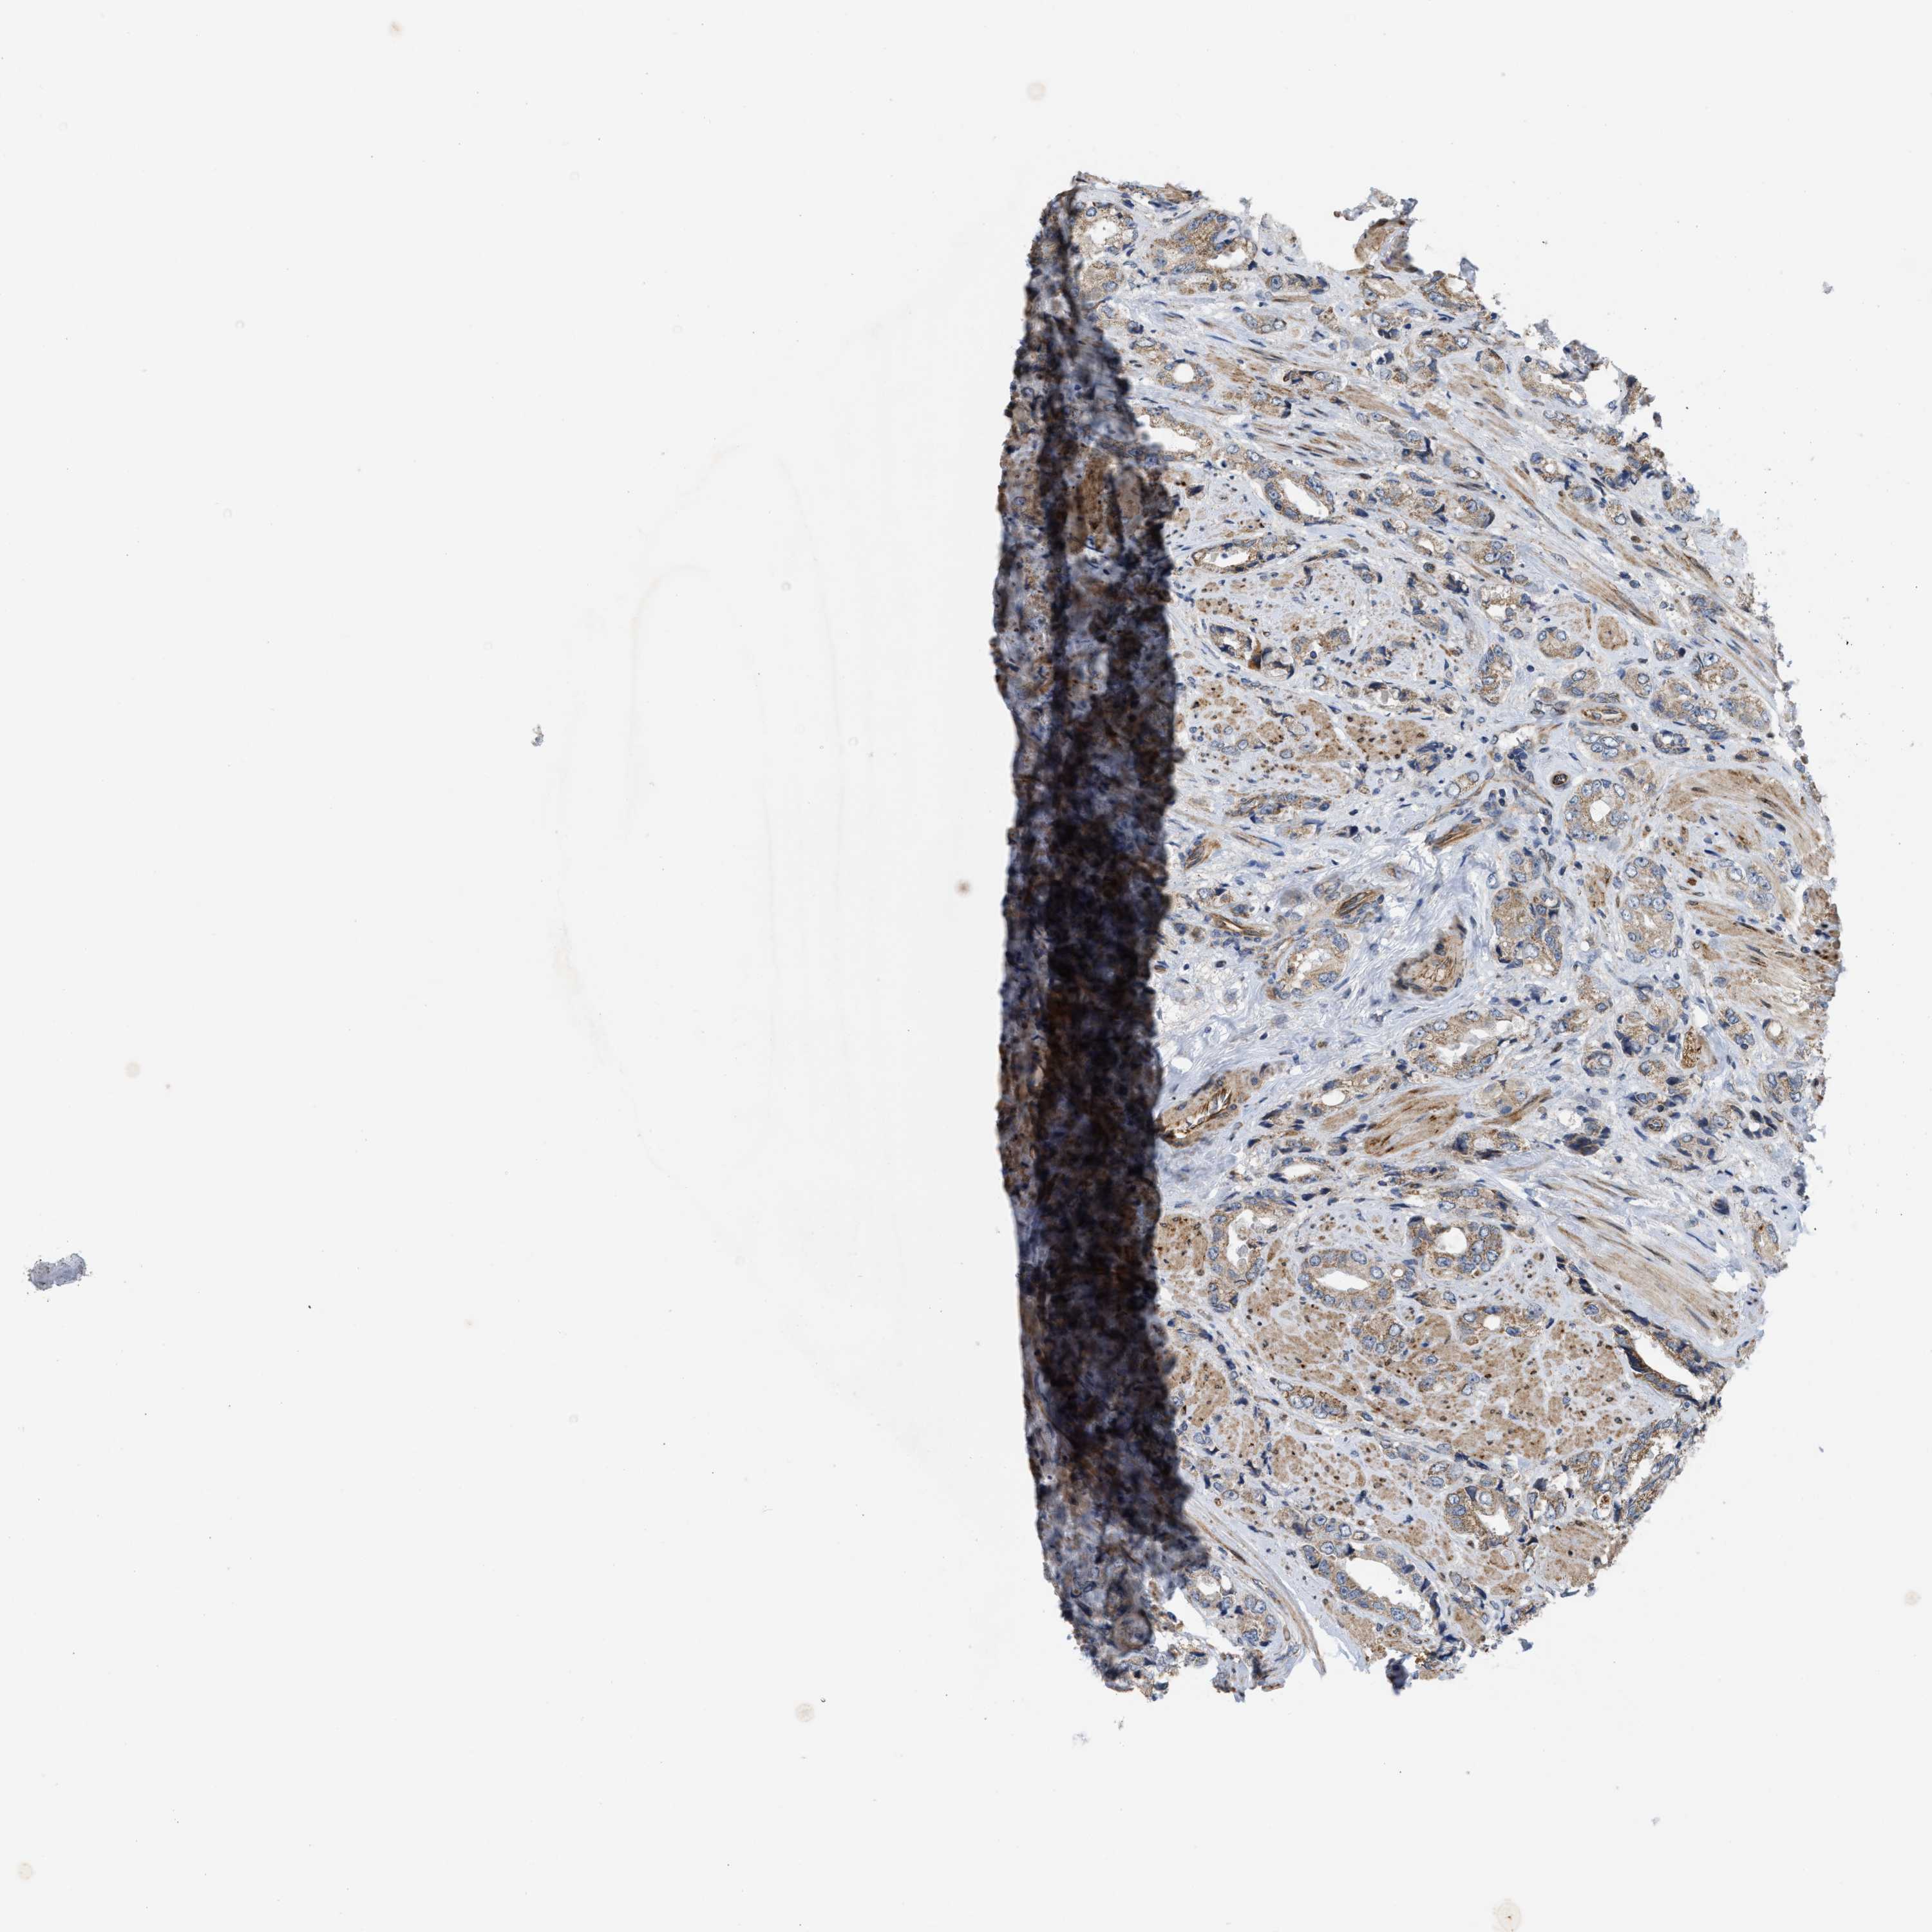

PROSTATE CANCER - Protein expressioni

A mouse-over function shows sample information and annotation data. Click on an image to view it in a full screen mode. Samples can be filtered based on level of antibody staining by selecting one or several of the following categories: high, medium, low and not detected. The assay and annotation is described here.

Note that samples used for immunohistochemistry by the Human Protein Atlas do not correspond to samples in the TCGA dataset.

Antibody stainingi

Antibody staining in the annotated cell types in the current human tissue is reported as not detected, low, medium, or high, based on conventional immunohistochemistry profiling in selected tissues. This score is based on the combination of the staining intensity and fraction of stained cells.

Each image is clickable and will lead to virtual microscopy that enables deeper exploration of all samples and also displays staining intensity scores, fraction scores and subcellular localization as well as patient and tissue information for each sample.

Antibody HPA019460

Staining

High

Medium

Low

Not detected

Intensity

Strong

Moderate

Weak

Negative

Quantity

>75%

75%-25%

<25%

None

Location

Nuclear

Cytoplasmic/membranous

Cytoplasmic/membranous,nuclear

Adenocarcinoma, High grade

Adenocarcinoma, Low grade